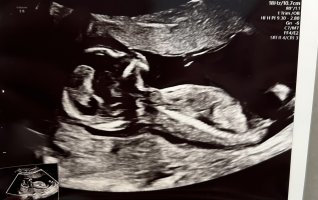

Vil du se om skull theory er mulig på mine bilder??Synes ikke nuben synes så godt? Litt gutt ifølge skull theory

Gjetter jente for moroskyldVil du se om skull theory er mulig på mine bilder??

Ser ut som guttSyns det er veldig vanskelig å se, altså. Noen som vil gjette? Første ul uke 11, andre uke 14.